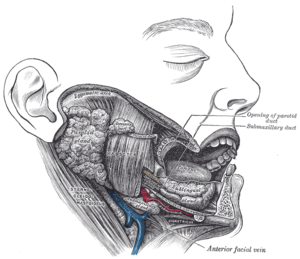

Masseter

De masseter bevindt zich aan de zijkant van de kaak. Hi...

Lippen

De lippen zijn twee organen van spierweefsel die de ing...